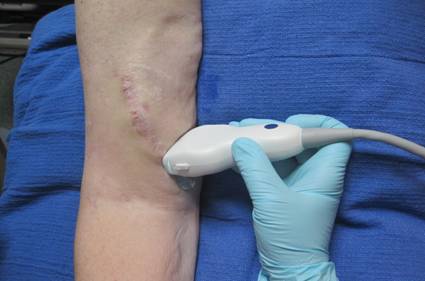

• Duplex / Ultrasound Exam: Duplex is a painless ultrasound exam to evaluate your AVF or AVG.